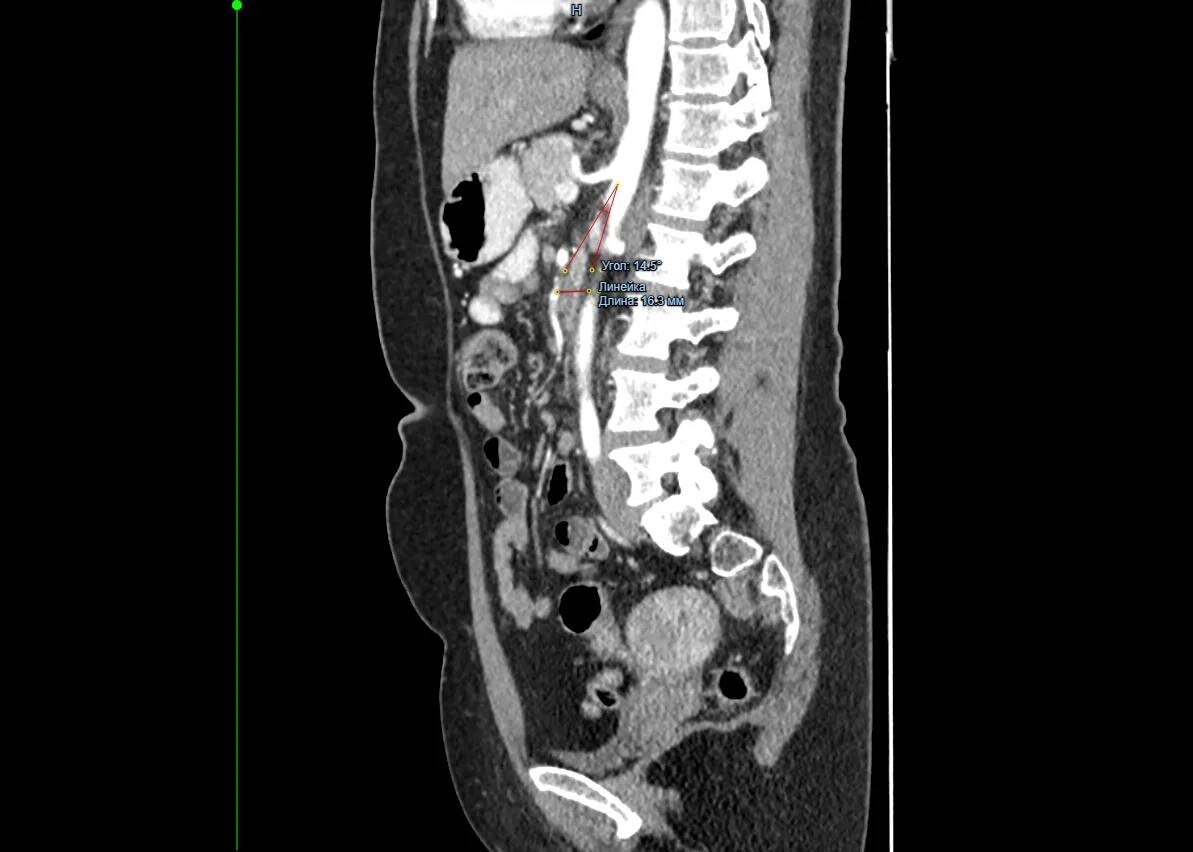

«Не могла нормально питаться»: хирурги прооперировали красноярку с редким заболеванием

Врачи хирургического отделения №3 Красноярской межрайонной клинической больницы №20 им. И.С. Берзона провели операцию 49-летней пациентке с синдромом Уилки. Из-за него женщина долго не могла нормально питаться и сильно похудела.